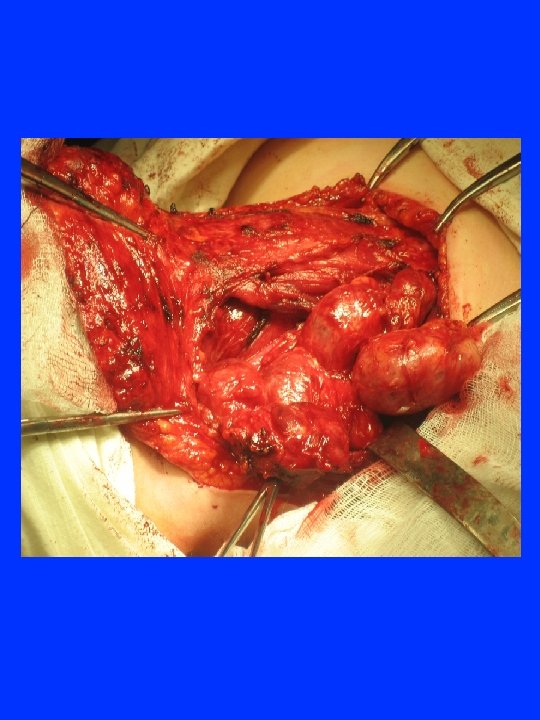

ЛАРИНГО-ТРАХЕАЛЬНАЯ ИНВАЗИЯ 33. 1% 17. 0% 9. 9% 4 - 20 21 - 40 41 - 60 61 - 84 возраст

ЛАРИНГО – ТРАХЕАЛЬНАЯ ИНВАЗИЯ РАКА ЩИТОВИДНОЙ ЖЕЛЕЗЫ